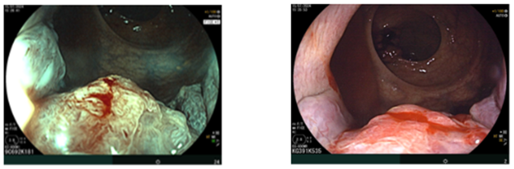

Nội soi đại–trực tràng (07/2024):

Ghi nhận hai tổn thương u sùi ở trực tràng, cách rìa hậu môn khoảng 5 cm và khoảng 10 cm. Tổn thương “phía trong” chiếm gần hết lòng trực tràng; tổn thương “phía ngoài” kích thước khoảng 3,0 cm. Ống hậu môn có đám tổn thương gồ ghề loang lổ.

Hình 2: Tổn thương gồ ghề loang lổ ở ống hậu môn

Giải phẫu bệnh (sinh thiết):

-         Trực tràng: ung thư biểu mô tuyến biệt hóa vừa.

-         Hậu môn: u tuyến ống, loạn sản độ thấp (tubular adenoma, low-grade dysplasia).